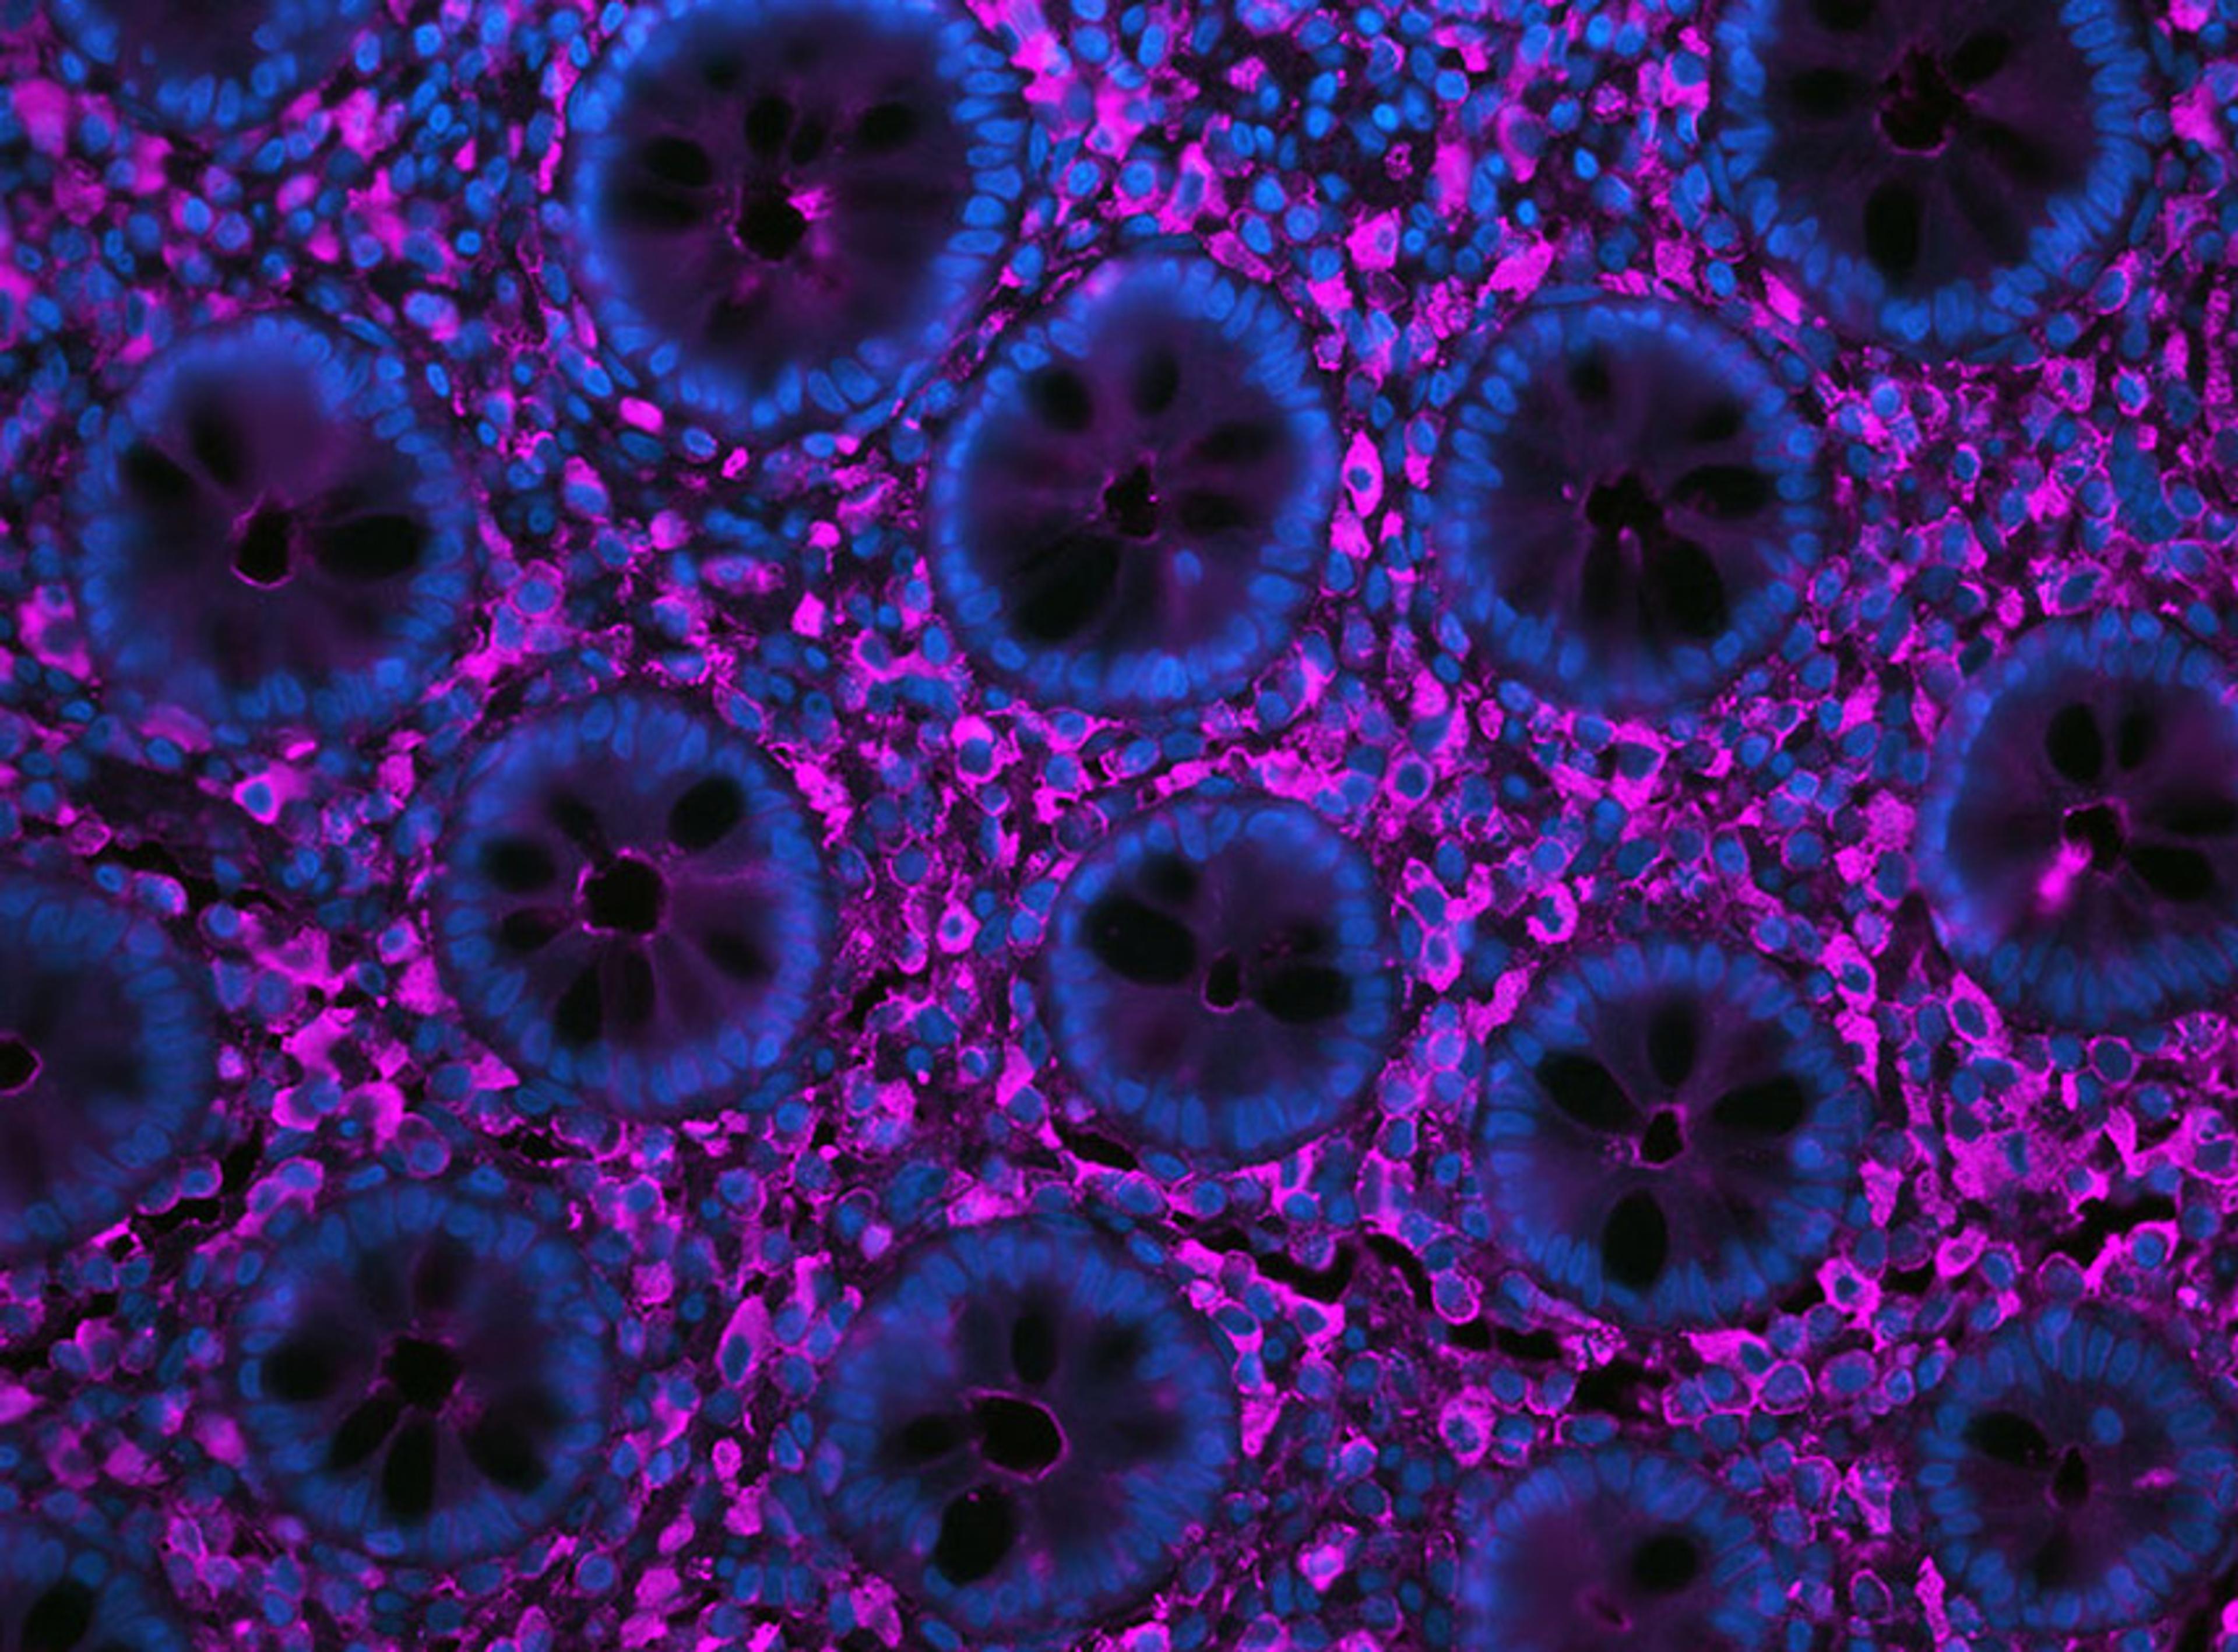

Quantification and characterization of glomeruli across diverse stains using HALO AI™

In this application note, Indica Labs highlights the potential for HALO® and HALO AI to quantify biomarkers, gene expression, and morphological changes in kidney disease, during development and in toxicological studies.

Robust identification of islets with variable morphology in H&E-stained pancreatic tissue using HALO AITM

In this application note, Indica Labs trains the HALO AITM VGG convolutional neural network (VGG-CNN) to identify islets within pancreatic tissue sections following H&E staining. It demonstrates how it is possible to build a robust classifier to accurately segment islets from surrounding exocrine tissue, irrespective of stain or morphological variability. This study highlights the potential for HALO AI to simplify the pathological evaluation of pancreatic tissue in metabolic research and toxicological pathology.